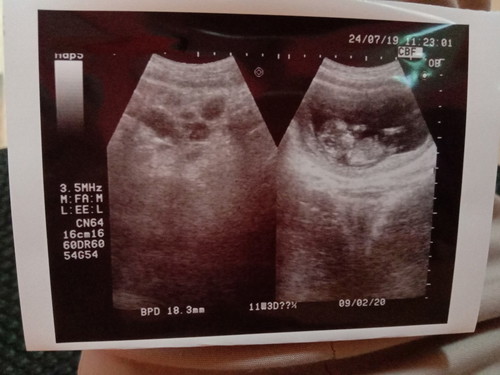

terdapat gambar bulatan di hasil USG

Assalamua'laikum... Usia kehamilan sy baru 13w5d tdi pagi baru usg di bidan terdekat bun pengen lihat perkembangan janin nya, tpi hasil nya terdapat bulatan sprt pada photo adakah bunda yg tau atau pernah mengalami hal yg sama , kondisi janin alhamdulillah sehat sudah terlihat jelas ... Nanti malam sy mau USG lgi ke dokter mudah*n tidak terjadi apa* dengan kandungan sy, mohon do'a nya ya bunda ?